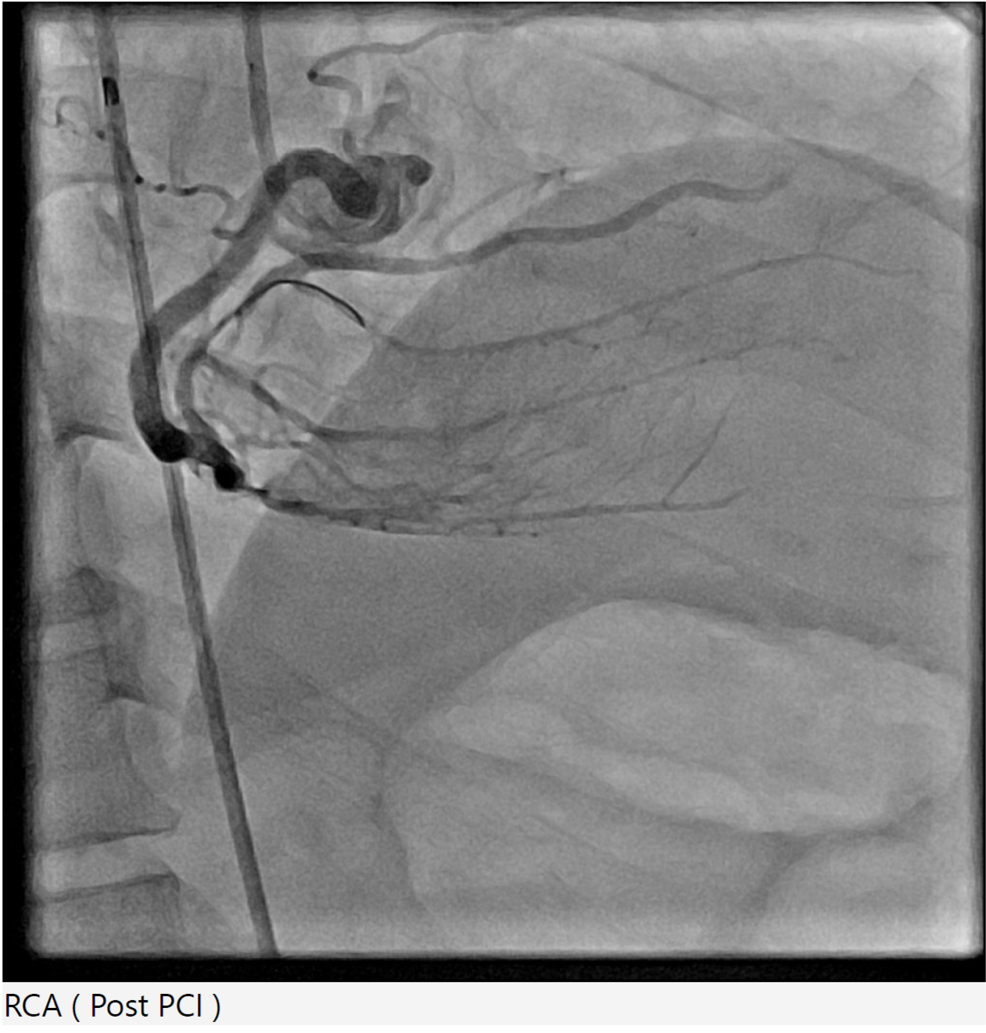

Right radial 6Fr JR 4.0 initially for antegrade RCA CTO attempt, subsequent switched to AL 1.0 for better support. CTO lesion crossed using Gaia Next 3 wire with Finecross microcatheter support, pre-dilatation using SC Sapphire 1.0 ¡¿ 8 mm balloon. However, guide catheter induced aorto-ostial dissection (Dunning Class II) occurred during catheter manipulation and contrast injection. The dissection was promptly recognized and proceed strategy of seal the dissection via ping pong technique. Second access via right femoral 6Fr long sheath due to tortuous iliac artery with JR 4.0, Sion Blue wire crossed to distal RCA. The ostial-proximal lesion is predilated with NC Trek 3.5 ¡¿ 12 mm balloon, then stented with Biofreedom 3.5 ¡¿ 24 mm and post dilate with NC Trek 3.5 ¡¿ 12 mm balloon. The mid to distal RCA lesion is prepared using SC Euphora 2.0 x 15 mm balloon with AL 0.75 catheter and Telescope guide extension support. Further predilate with Lacrosse Aperta 3.0 x 13 mm and NC Sapphire 3.0 x 10 mm balloon. Distal RCA treated with DCB Essential Pro 3.0 ¡¿ 40 mm. Proximal to distal RCA stented with Biofreedom 3.5 ¡¿ 24 mm and Biofreedom 3.5 ¡¿ 36 mm (overlapping from ostial to distal). Final post-dilatation with NC Trek 3.75 ¡¿ 8 mm (mid–distal) and NC Sapphire 4.5 ¡¿ 8 mm (proximal). Final IVUS guidance via AL 0.75 guiding catheter and Telescope guide extension showed good result without hemodynamic compromise. Total contrast 240 mL, fluoroscopy 132 mins.

mov-series-105 final RCA.wmv

This case highlights a rare but significant complication of catheter-induced RCA aorto-ostial dissection during PCI for chronic total occlusion. RCA CTO lesions pose technical challenges due to heavy calcification, tortuous course, and limited guide support. In this case, deep seating of the guiding catheter during contrast injection likely precipitated an aorto-ostial tear. Timely recognition and immediate sealing with overlapping DES — guided by IVUS — prevented progression into the ascending aorta and avoided emergent surgical conversion.